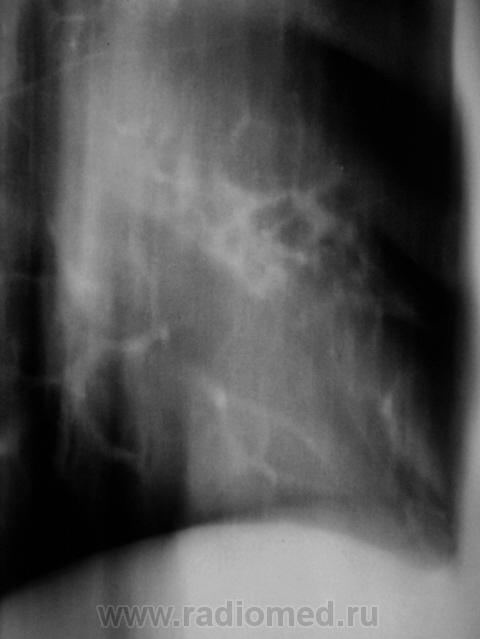

Томограммы.

1.pc170025.jpg2.pc170026.jpg3.pc170026a.jpg3.pc170027.jpg5.pc170028.jpg6.pc170028a.jpg7.pc170029.jpg8.pc170029a.jpg